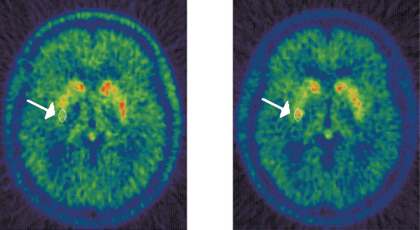

本站编译:荷兰科学家目前发现,无任何症状的,不为人察觉的轻微中风将使患者得早老性痴呆症的几率大为增加。研究表明,通过核磁共振造影术发现的轻微中风者,其演变为早老性痴呆或其它类型痴呆症的几率是正常人的2.3倍。

这则全球第一例关于“无声中风”的报告,刊登在上周四出版的《新英格兰医学期刊》上。医学专家认为中年人群应加强锻炼、均衡饮食、告别香烟,从而减轻体重及降低体内血压、胆固醇及血糖等指标。同时,报告显示了脑血管狭窄与中风及痴呆症之间的内在联系,而无声中风则被认为是早老性痴呆的一种重要讯号。